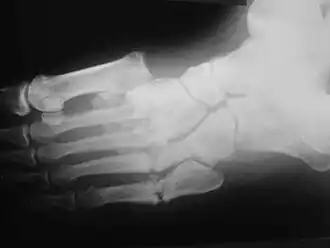

Artropatia neuropática, osteoartropatia neuropática ou articulação de Charcot refere-se à degeneração progressiva de uma articulação dos pés, pernas ou pélvis (articulações responsáveis por carregar o peso do corpo). É um processo marcado por destruição óssea, reabsorção óssea, e eventual deformidade devido a perda de sensibilidade ao longo de muitos meses ou anos. A primeira descrição foi feita por Jean-Martin Charcot,

A apresentação clínica varia dependendo do estágio da doença, começa com um edema leve e evolui a um inchaço e deformidade cada vez maiores. Inflamação, eritema, dor e aumento da temperatura da pele (3-7 graus Celsius) ao redor da articulação podem ser perceptíveis ao exame físico. Raios-X podem revelar reabsorção óssea e alterações degenerativas na articulação. Esses achados na presença de pele íntegra e perda de sensibilidade tátil protetora servem para diagnósticos da artropatia de Charcot aguda.